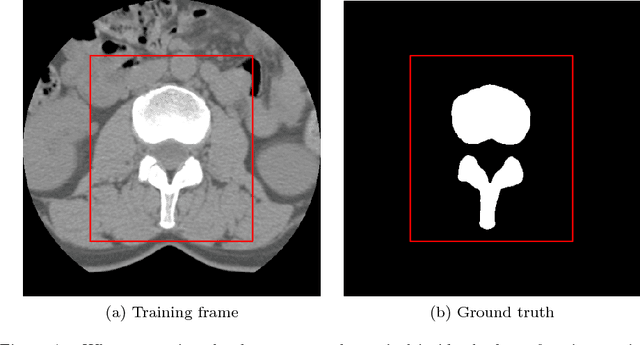

There has been a significant increase from 2010 to 2016 in the number of people suffering from spine problems. The automatic image segmentation of the spine obtained from a computed tomography (CT) image is important for diagnosing spine conditions and for performing surgery with computer-assisted surgery systems. The spine has a complex anatomy that consists of 33 vertebrae, 23 intervertebral disks, the spinal cord, and connecting ribs. As a result, the spinal surgeon is faced with the challenge of needing a robust algorithm to segment and create a model of the spine. In this study, we developed an automatic segmentation method to segment the spine, and we compared our segmentation results with reference segmentations obtained by experts. We developed a fully automatic approach for spine segmentation from CT based on a hybrid method. This method combines the convolutional neural network (CNN) and fully convolutional network (FCN), and utilizes class redundancy as a soft constraint to greatly improve the segmentation results. The proposed method was found to significantly enhance the accuracy of the segmentation results and the system processing time. Our comparison was based on 12 measurements: the Dice coefficient (94%), Jaccard index (93%), volumetric similarity (96%), sensitivity (97%), specificity (99%), precision (over segmentation; 8.3 and under segmentation 2.6), accuracy (99%), Matthews correlation coefficient (0.93), mean surface distance (0.16 mm), Hausdorff distance (7.4 mm), and global consistency error (0.02). We experimented with CT images from 32 patients, and the experimental results demonstrated the efficiency of the proposed method.